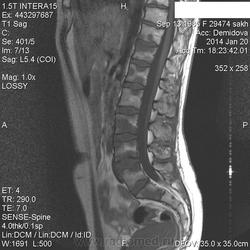

Вторая пациентка:

В телах позвонков определяются множественные очаги и фокусы разной степени интенсивности понижения МР-сигнала по Т1, Т2 ( первые 2 картинки), неоднородного повышения по Т2 с жироподавлением ( третьи картинки).

Контрастирование  не проводили.